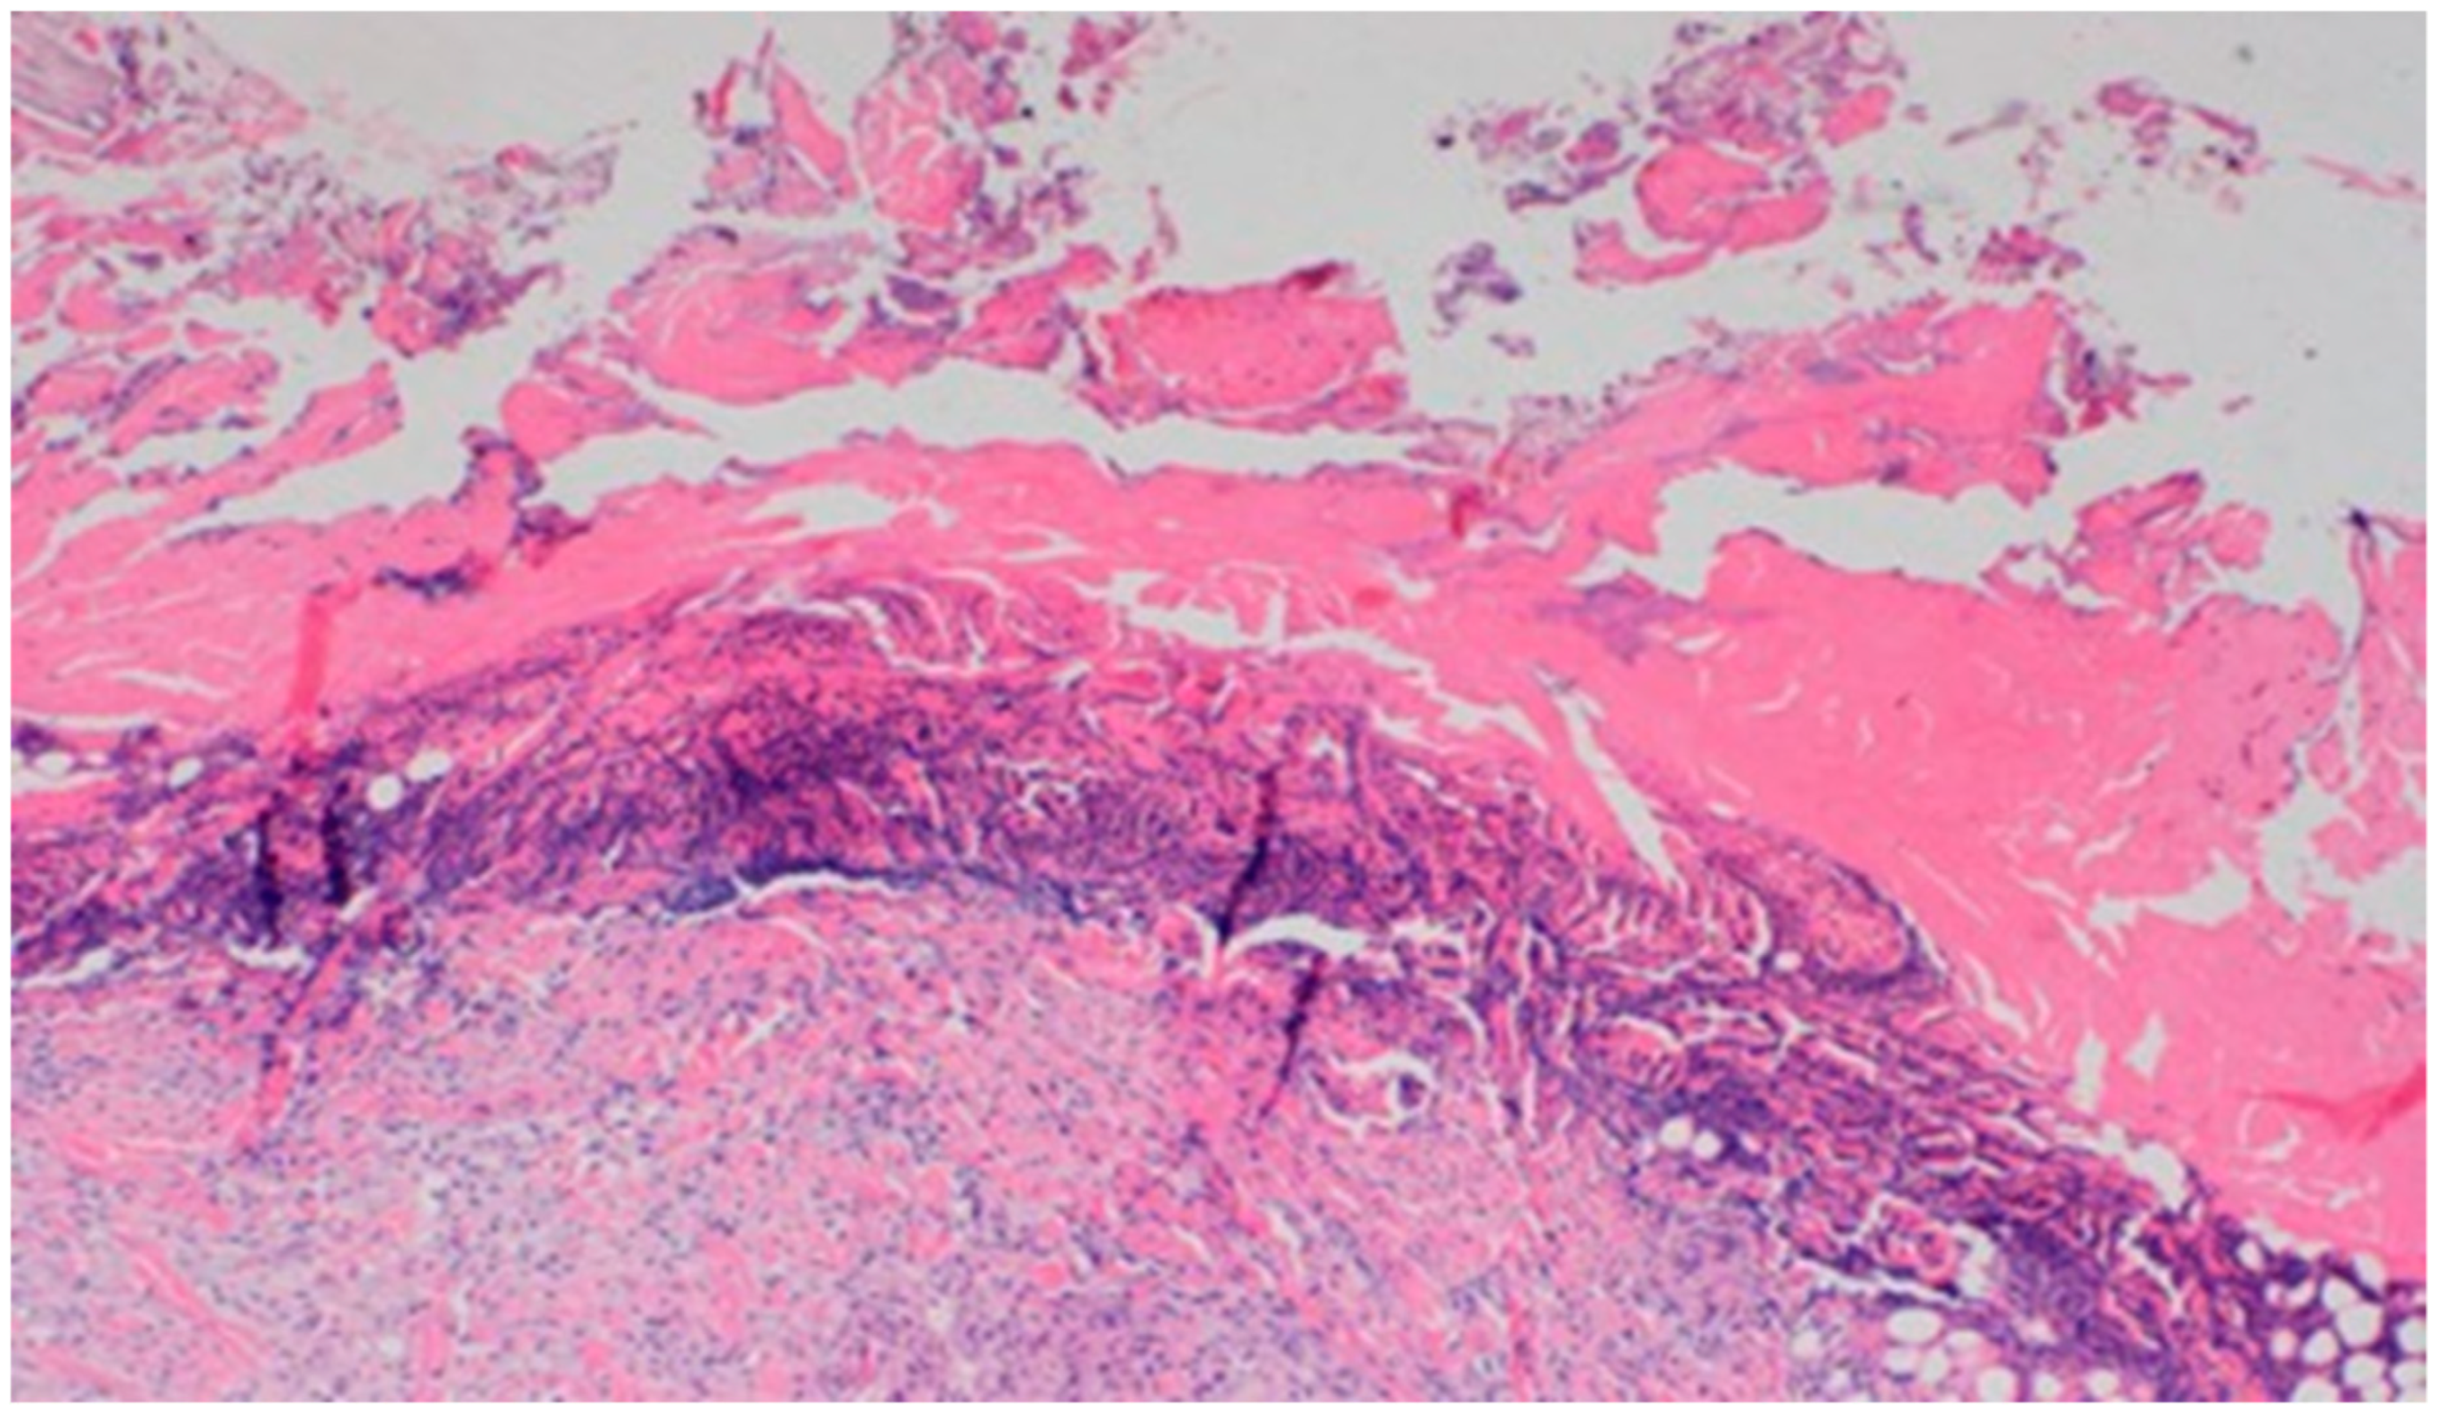

On day 5 of the experiment, slight differences in the wound healing process were observed. Inflammation was present in all wounds and the surrounding tissues, however, with a different intensity, type and depth of infiltration. In group D1, treated with the 1% propolis ointment, there was a moderately dense granulocytic infiltration reaching the dermis. Wounds in group D2, treated with the 1% nanosilver ointment, were characterized by a granulocytic infiltration with a low density and depth of infiltration reaching the dermis. In wounds treated with a mixture of 1% propolis and 1% nanosilver, there was a large granulocytic inflammatory infiltration reaching the depth of the adipose tissue. Wounds treated with sulfathiazole were characterized by a small, mixed infiltration reaching the dermis. On day 5 of the treatment, all wounds from the experimental and control groups did not show any epidermization features. Superficial necrosis was low in the experimental groups and a high degree of necrosis was observed in the sulfathiazole-treated control group. The histopathological findings from day 5 are presented in Table 8 and Figure 13 and Figure 14.

Figure 14. Necrosis, with granulocytic inflammatory infiltration (100×, H-E), in the wound treated with sulfathiazole, on day 5.